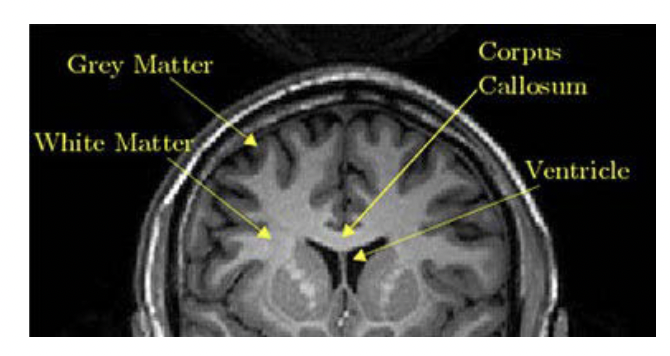

Grey matter, White matter, Sulci, Gyri

A

Superficial layer = see grey matter

gyri - high points - outpuchings

Suci - valleys - invaginatiions

Sulci/gyri = differentiates us with mice (mice have smooth brain)

Grey Vs. White matter

Grey = where neurons sit

- Grey = split into motor nuerons and intervenous nuerons

White = Myelin (primarily form oligiodendricytes)

- has tracks of nuerons

Grey matter = surounded by white matter

Imaging of White and grey matter

Can see diference in imaging - grey and white matter are different radiologicaly

Image -

1. White layer around top = fat layer within the skull

2. can see ventrical (has CSF - black part is CSF)

3. Thin grey around the gryi = Dura layer suroudning the brain